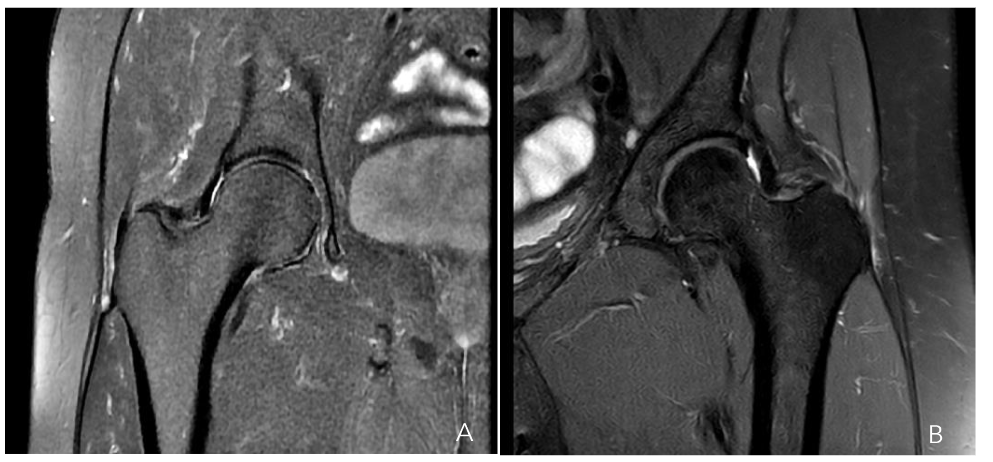

Given that this condition involves tendon insertion (enthesis) in an area with poor blood supply, we utilize the intermediate portal to perform transtendinous perforations in the degenerated tendon regions Figure 5. These perforations are directed towards the greater trochanter to encourage the development of new blood vessels and enhance blood flow, ultimately promoting healing of the lesion, indicating that this method has yielded exceptional results in both clinical evaluations and imaging examinations for partial tears of up to 25% of the total thickness, as illustrated in Figures 6a-b.

Figure 6a-b. Hip MRI scan showing a partial gluteus medius tear (a) and a gluteus minor tear (b)

The selection of an appropriate treatment modality becomes more complex when lesions affect between 25% and 50% of the thickness Figure 7. As previously noted, these lesions are situated medial to the gluteus medius tendon, demonstrating tendon continuity in the most lateral region. Direct repair of this lesion would require the disinsertion of a healthy gluteus medius tendon, which is suboptimal. Cutting one healthy tendon to repair another would, at best, result in scar tissue formation, which would not possess the same functionality as native tissue. Consequently, in this subset of lesions, augmentation with a biological collagen patch is employed, in addition to the technique described for the two previous groups.

Figure 7. Hip MRI scan showing a 30% rupture of the gluteus medius and minor tendons

Our group conducted a prospective study by incorporating the REGENETEN® patch as a single augmentation technique from 2019 to 2024 with a minimum follow-up of 6 months⁴³. The study population comprised patients who underwent hip surgery for tendinopathy refractory to conservative treatment, defined as failure to respond to NSAIDs, three courses of physiotherapy, and a symptom duration exceeding 6 months. In patients with a symptom duration of less than 6 months, surgical intervention was indicated in the presence of 30% to 50% rupture of the gluteus medius minimus tendon complex. All patients underwent preoperative MRI, which was subsequently compared with imaging performed 6 months postoperatively, demonstrating complete healing of the tendon.